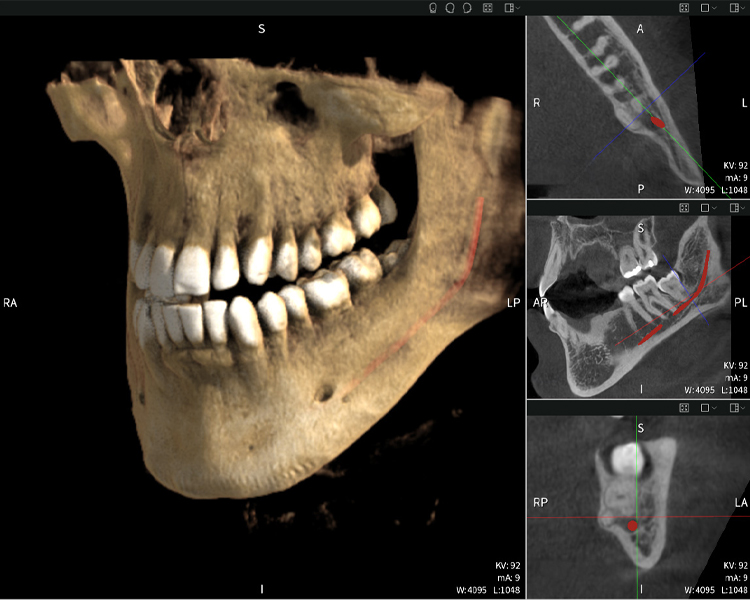

Below you will find a case from Dr. med. dent. Oliver A. Centrella, in which the CBCT images obtained with Seethrough Max provided crucial information on the complex anatomy and the critical relationship between the wisdom teeth and the inferior alveolar nerve. In this case, there is a indication for the surgical removal of the wisdom teeth.

Figure b: Imaging results of Seethrough Max, in front of a black background.

Figure b

Figures b–d show various views of a 3D reconstruction of the mandible, providing a comprehensive overview of the mandibular anatomy, the position of the nerves in relation to the teeth, and allowing assessment of tooth symmetry and alignment.

Figure d shows the previously treated tooth 48, with its crown removed, and its roots left in proximity to the nerve, illustrating the high risk of nerve damage.